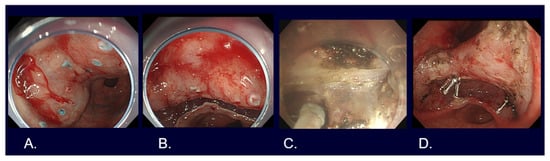

5. Types of Endoscopic Resection for Early Gastric Cancer